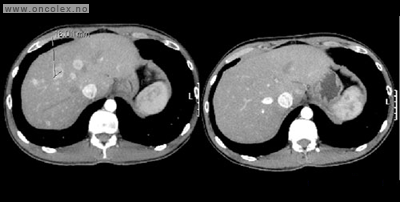

Bildeeksempler